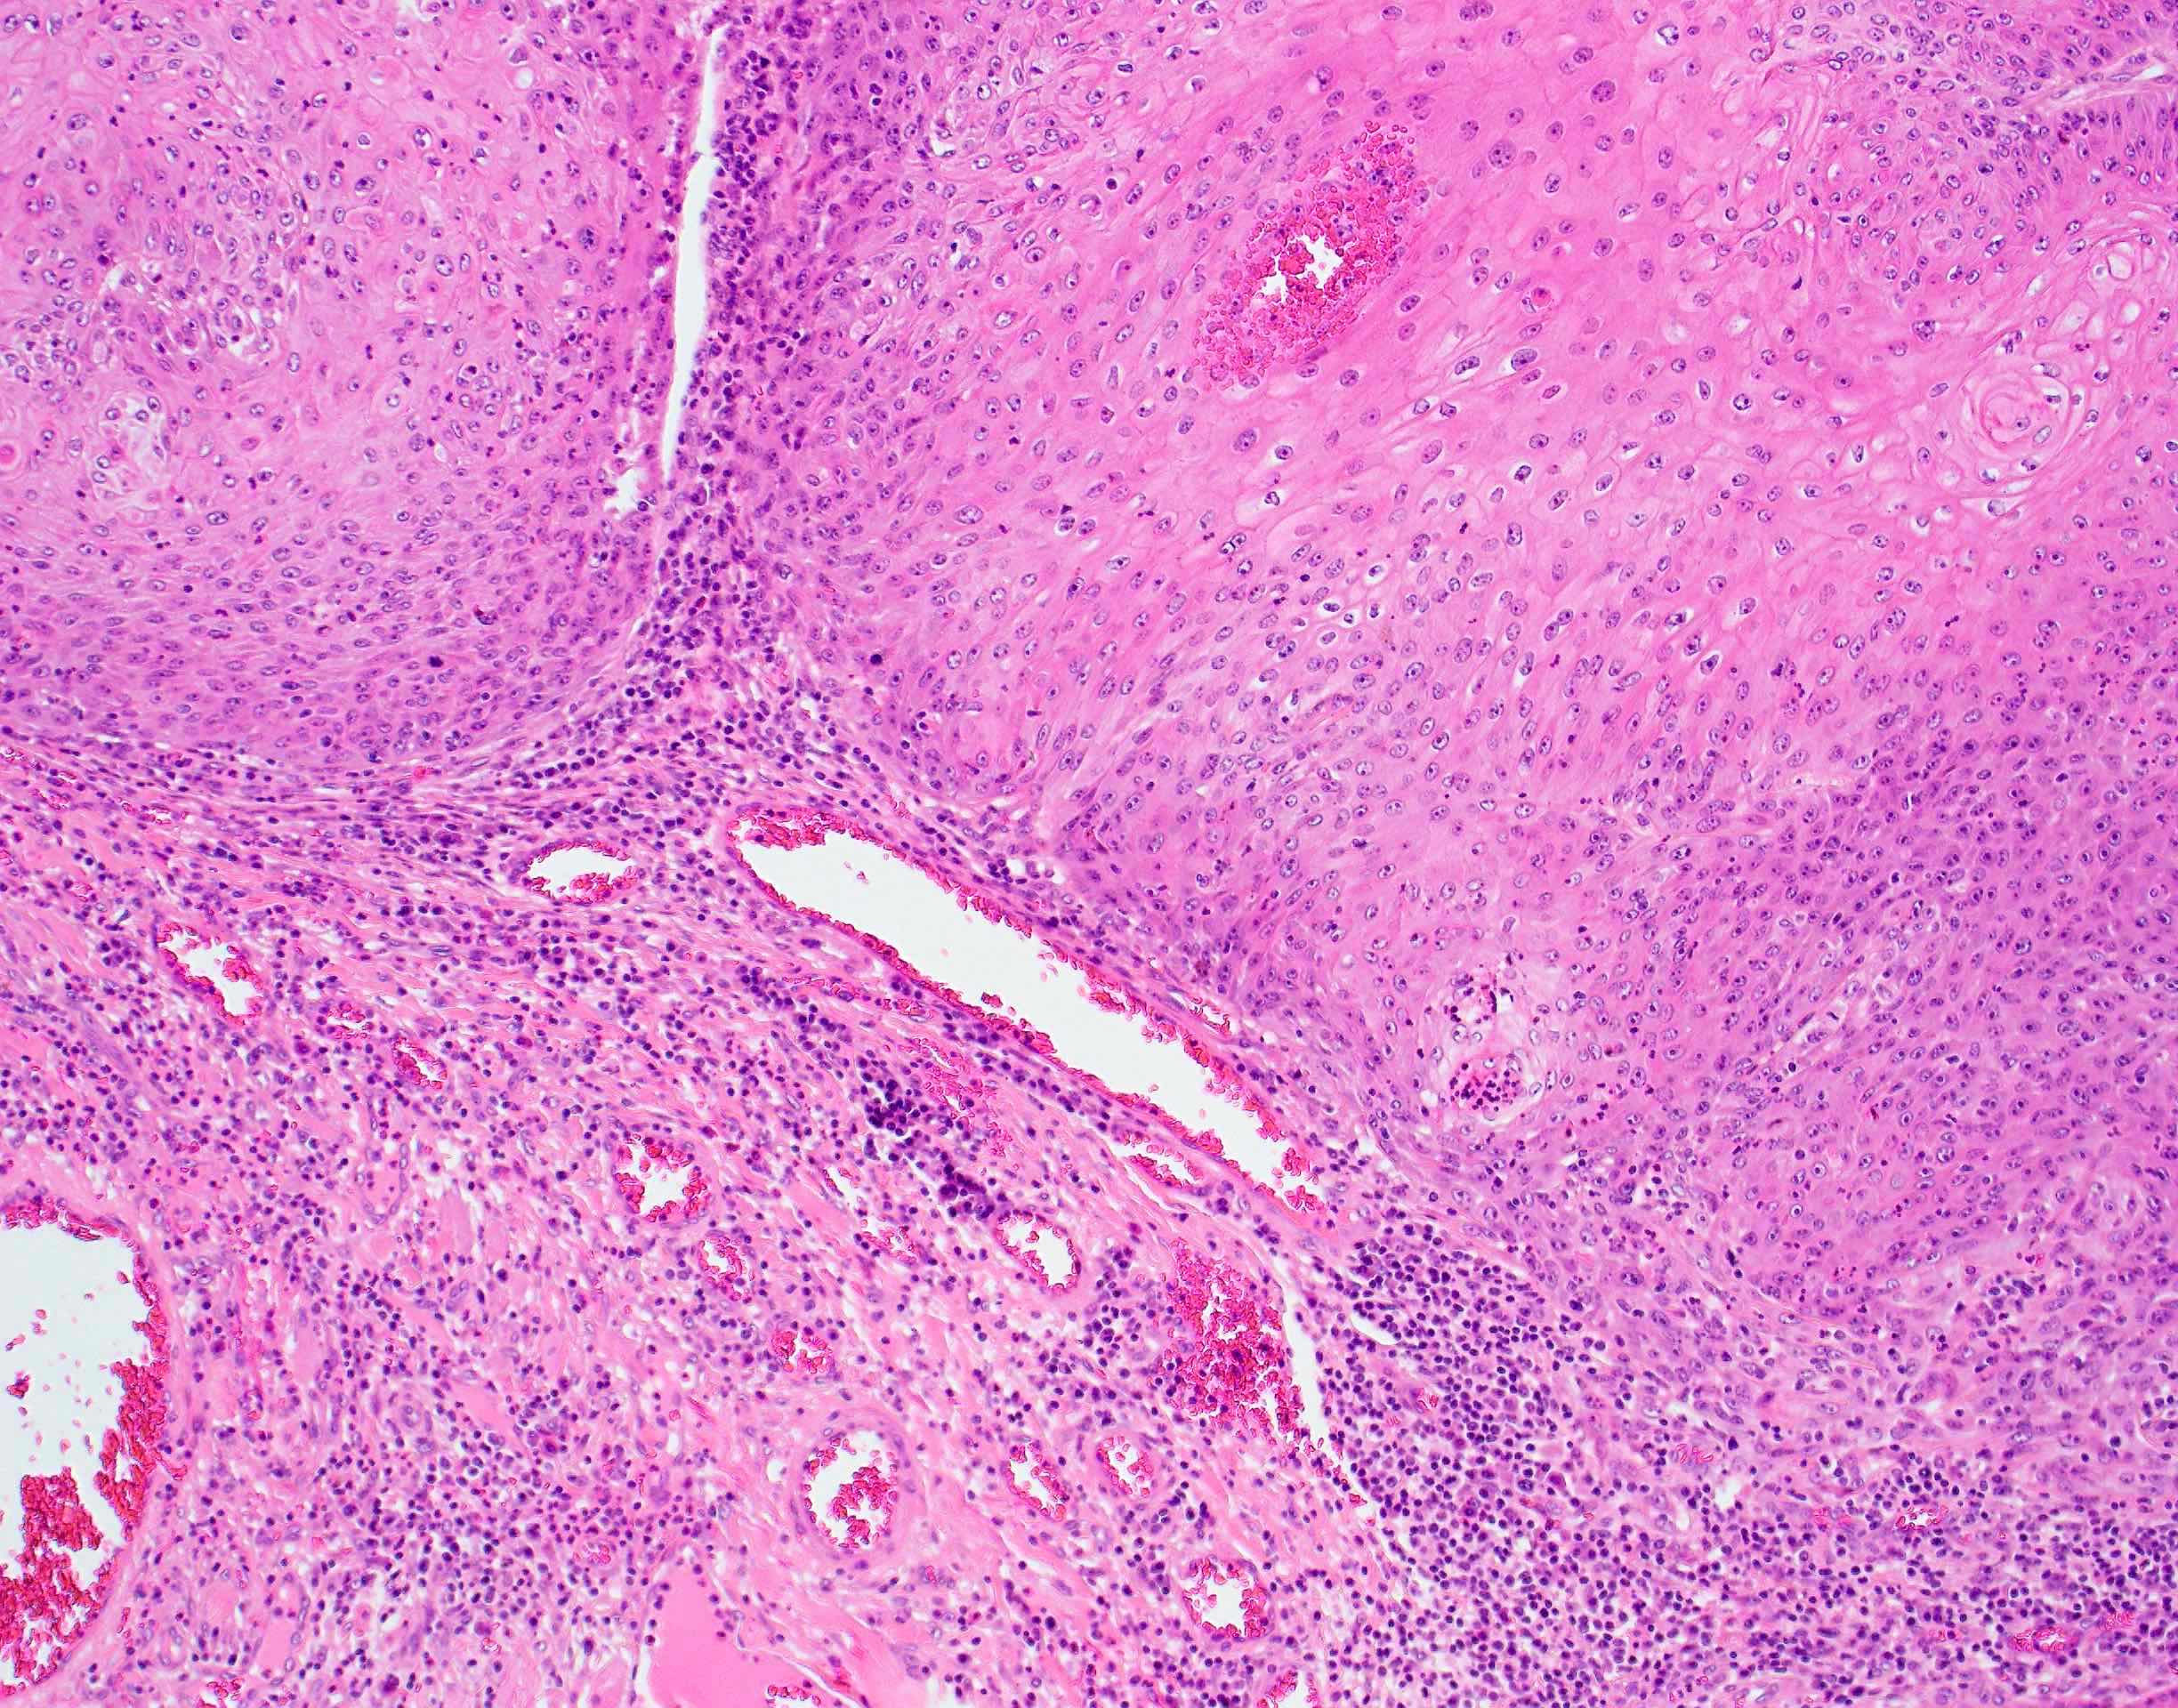

- Lymphoepithelial carcinoma (nonnasopharyngeal) (Head Neck Pathol 2011;5:327)

- Cohesive tumor nests of nonkeratinising epithelioid cells with prominent intermixed reactive lymphoplasmacytic infiltrate

- Present at high stage with metastases

Microscopic (histologic) images

Contributed by Ruta Gupta, M.B.B.S., M.D.